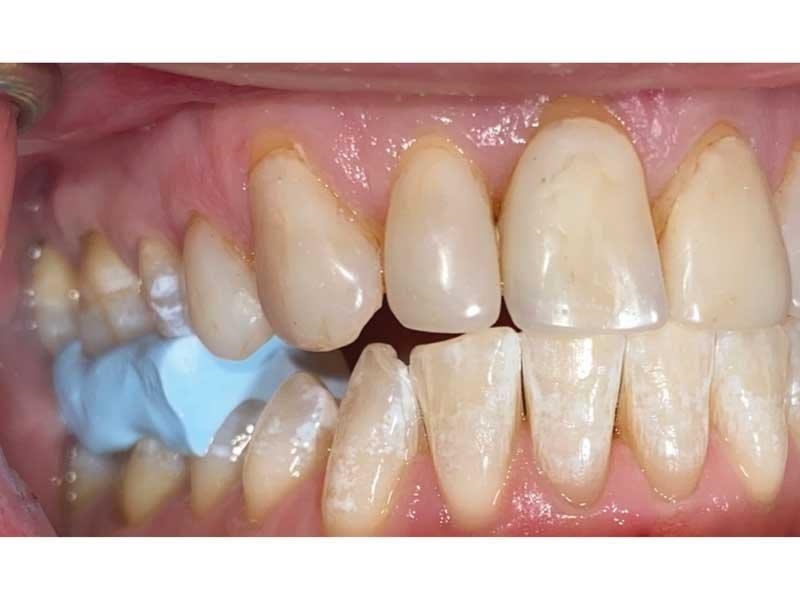

Meet Lorraine, who came into my office to “redo her bonding.” Lorraine had some upper anterior teeth done years ago with resin, which now was dull, stained and breaking down (Figs. 1–3). She had an amount of money in mind that she thought it would cost. She was very wrong.

Fig. 3

Challenge 2: Number of teeth. Lorraine had eight teeth with “bonding” on them, so she assumed we’d be talking about doing eight of something, whether resin or porcelain. But her buccal corridor spaces were dark and suggested narrowed arches, and when I brought that up, Lorraine said she had always wanted a “wider” smile.

The big challenge: Retruded and overclosed. Lorraine looked retruded and overclosed, so I started to ask her about headaches, jaw issues and chronic pain. As we talked, she revealed that she had been in severe pain her whole life. She had all the signs and symptoms of TMD and had been to multiple doctors, pain clinics, alternative medicine practitioners, massage therapists, chiropractors, osteopaths … you name it.